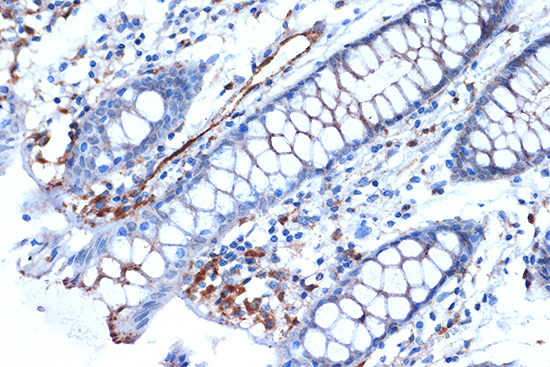

Syntenin Rabbit mAb

• appl_detail:

IHC 1:50 - 1:200